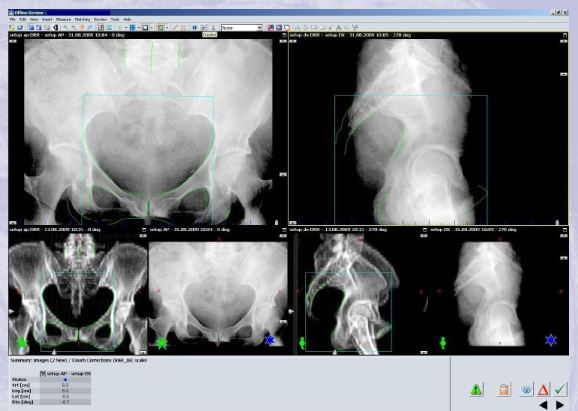

OBI

- Před každou frakcí

- 2 ortogonální snímky (AP a DX) srovnávány s referenčním DRR

- Nastavení na kostěné struktury

- AP: horní a dolní raménka stydkých kostí, foramina obturatoria, symfýza

- DX: dolní okraj symfýzy, hrboly sedacích kostí, os sacrum